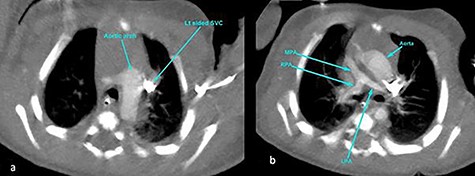

CT angiography thorax showing the left-sided aortic arch (a) and inverse relationship between ascending aorta and pulmonary artery. The MPA origin is atretic with hypoplastic RPA and LPA compared with the aorta (b). SVC, superior vena cava; RPA, right pulmonary artery; LPA, left pulmonary artery.